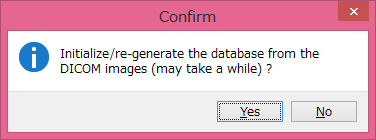

最後に「[Re]-initialize database」ボタンを押します。

![]()

DICOM画像をデータベースに入れて良いかどうか聞いてきます。

「Yes」を押してください。

STEP1で、データベースに、テーブルが存在しているかどうか確認しています。

failedとErrorが出ていますが、これはデータベースにまだ何もテーブルが無い状態だからです。

CONQUESTが自動でpostgreSQLのデータベースにテーブルを作り、そのテーブルにDICOM画像の情報を格納してくれます。